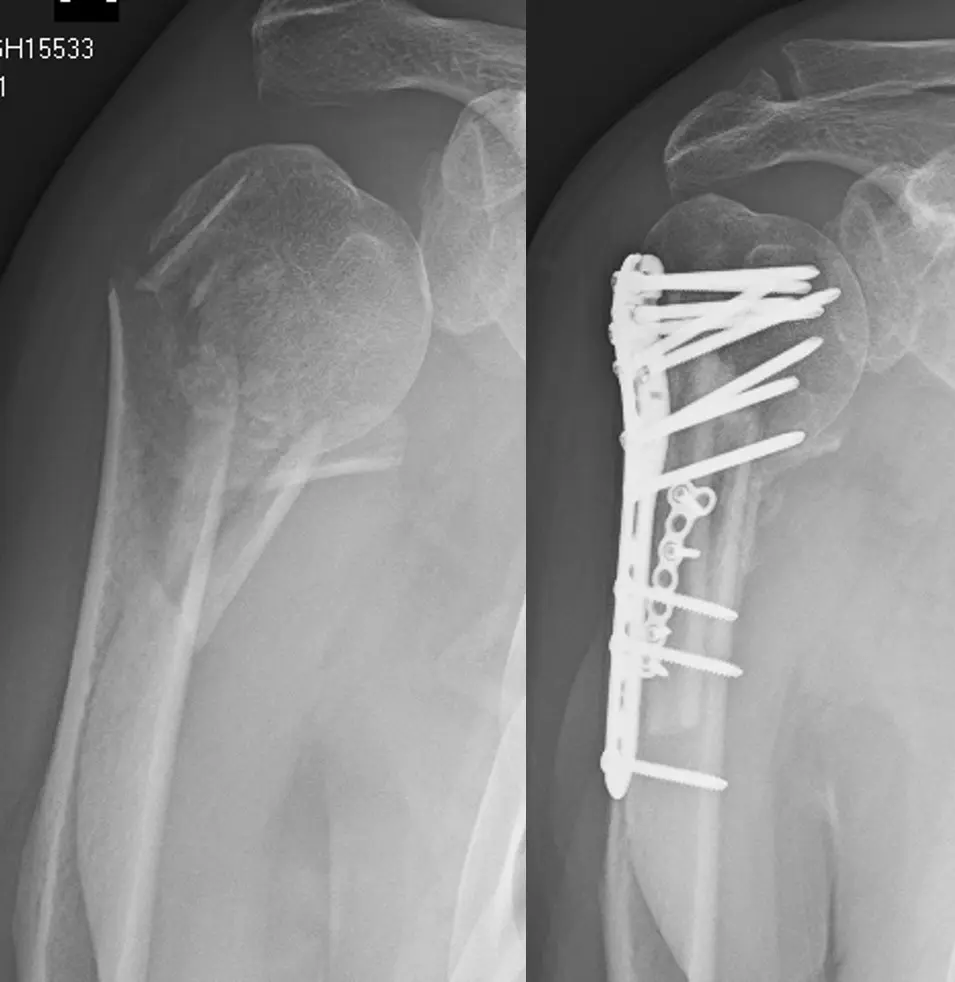

Fracture Care

Total Shoulder Replacement – Before and After Images